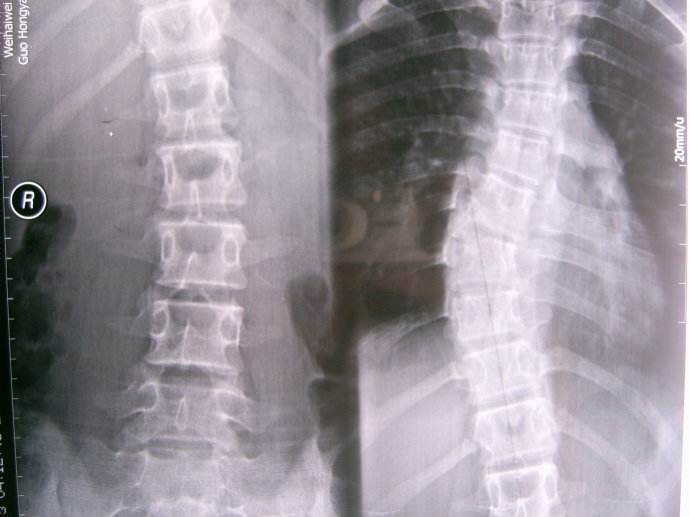

正常人的脊柱从后面看应该是一条直线,并且躯干两侧对称。如果从正面看有双肩不等高或后面看到有后背左右不平,就应怀疑“脊柱侧弯”。这个时候应拍摄站立位的全脊柱X线片,如果正位X线片显示脊柱有大于10度的侧方弯曲,即可诊断为脊柱侧凸。轻度的脊柱侧凸通常没有明显的不适,外观上也看不到明显的躯体畸形。较重的脊柱侧凸则会影响婴幼儿及青少年的生长发育,使身体变形,严重者可以影响心肺功能、甚至累及脊髓,造成瘫痪。轻度的脊柱侧凸可以观察,严重者需要手术治疗。脊柱侧凸是危害青少年和儿童的常见疾病,关键是要早发现、早治疗。

青少年特发性脊柱侧凸的角度如果胸弯超过50°或者腰弯超过40°,就有持续进展的风险。即使进入成人期,侧弯也还是会缓慢加重(每年大约增加2°-3°)。所以对于胸弯角度超过50°或者腰弯超过40°的特发性脊柱侧凸,建议手术治疗。

对于40°-50°之间的胸弯和35°-40°之间的腰弯是否要手术有一定的争议性,需要结合患者的具体情况,如侧弯类型,生长发育潜能等因素综合判断。

术前:11.png12.png  术后